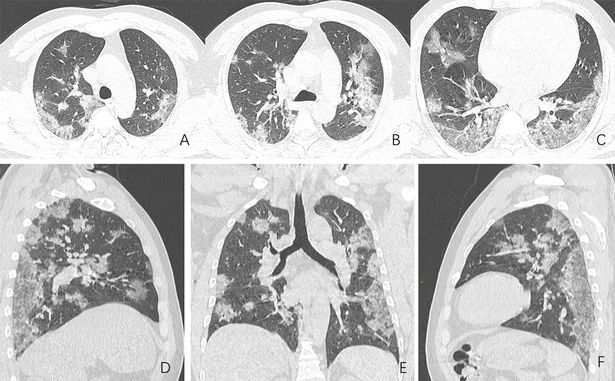

Đến phòng cấp cứu của bệnh viện, bạn đã được xét nghiệm và gửi đến một khu cách ly. Khi các bác sĩ chờ đợi kết quả cho corona, họ tiến hành chụp CT phổi cho bạn. Trên phim kết quả, các bác sĩ nhìn thấy những tổn thương kính mờ, những đặc trưng khó có thể lẫn đi đâu của tình trạng viêm phổi.

Phổi của bạn trắng đục giống như những tấm kính cửa số nhà tắm được cố tình làm mờ để không ai có thể nhìn vào bên trong. Các đốm mờ ấy chính là do chất lỏng tích tụ lại trong phổi, và ở đó, trận chiến của hệ miễn dịch đang diễn ra khốc liệt nhất.

Bạn không chỉ mắc Covid-19 mà bệnh còn tiến triển nặng đến một tình trạng viêm phổi nguy hiểm, đe dọa tính mạng được gọi là hội chứng suy hô hấp cấp tính hay ARDS.